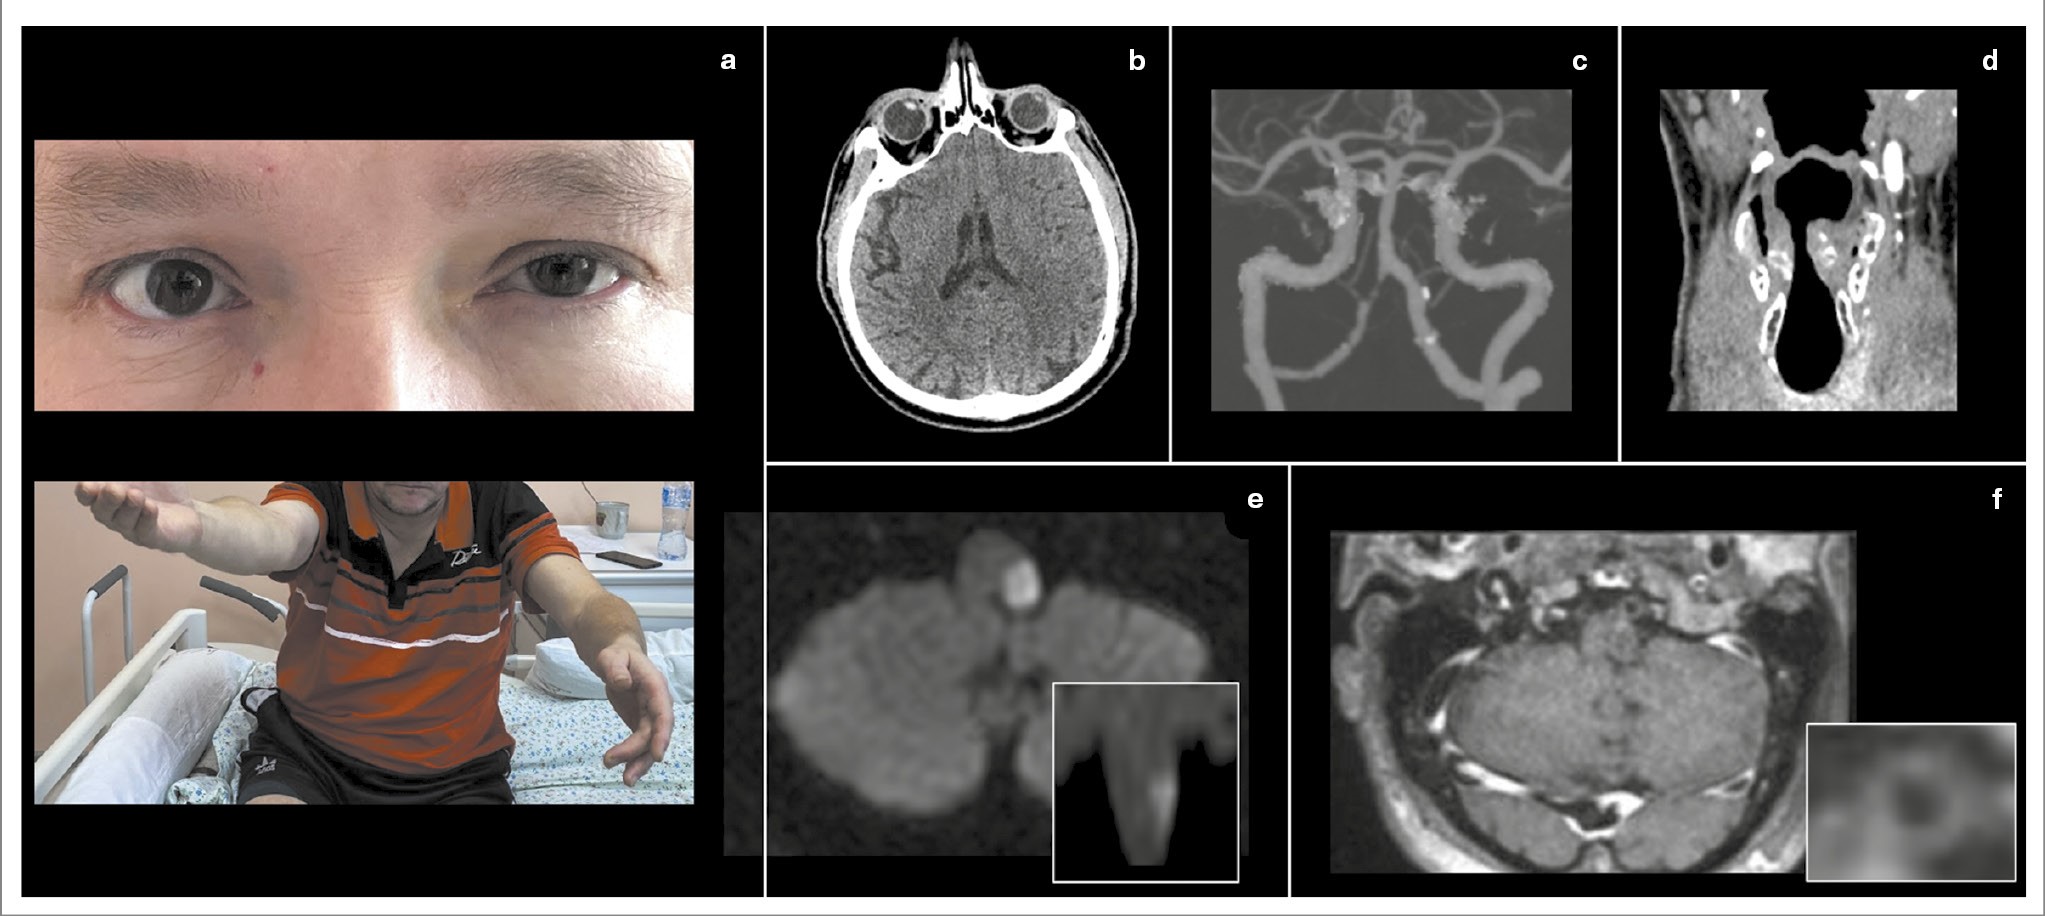

Рис. 2. ЛМИ вследствие диссекции позвоночной артерии. Пациентка 41 года. В анамнезе – синдром Вольфа–Паркинсона–Уайта, радиочастотная катетерная аблация и дефект межпредсердной перегородки по типу sinus venosus. 24 января 2024 г. после длительной поездки на автомобиле у пациентки возникли головокружение, боль в затылочной области, гнусавость голоса, онемение лица справа, снижение чувствительности и чувство жжения в левых конечностях. В течение месяца беспокоила боль в шее, за 5 дней до поступления проходила лечение у стоматолога. Поступила через 2 ч от начала заболевания. При поступлении выявлен синдром Горнера справа (a), горизонтально-торсионный нистагм, направленный влево, положительный OLD-тест справа, легкая дизартрия и дисфагия, снижение болевой и температурной (в больше степени) чувствительности в левой половине тела, выраженная туловищная атаксия. Выполнена КТ головного мозга, выявлена выраженная содружественная девиация глаз вправо – RadOLD (d). При проведении КТА выявлена окклюзия III и IV сегментов правой позвоночной артерии с паттерном «скорлупа арахиса» (гиподенсивный просвет и накопление контраста стенкой горизонтального сегмента артерии); b, а также медиальное смещение правой голосовой связки, свидетельствующее о ее парезе (c). Через 3 дня дисфагия регрессировала. На 5-е сутки выполнена МРТ головного мозга, позволяющая визуализировать правосторонний дорсолатеральный медуллярный инфаркт (d) и признаки интрамуральной гематомы стенки III сегмента левой позвоночной артерии как признак диссекции (e).